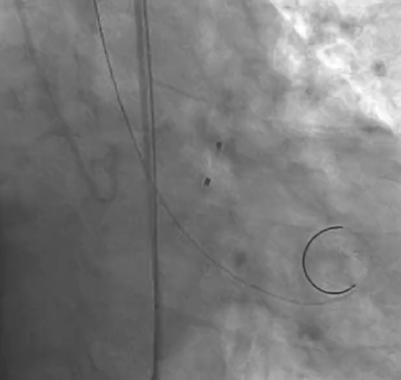

主动脉根部造影提示瓦氏窦整体形态偏小,决定给予冠脉保护

导丝左冠保护

术前右冠造影

导丝跨瓣